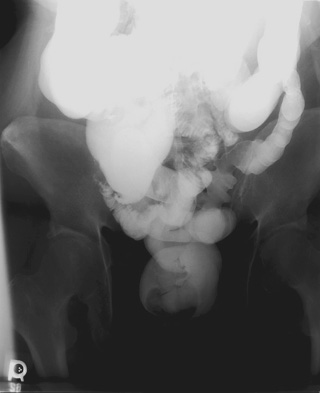

- Prone angle view of rectosigmoid - patient prone, 35° cephalad central

ray, 14" x 17" cassette